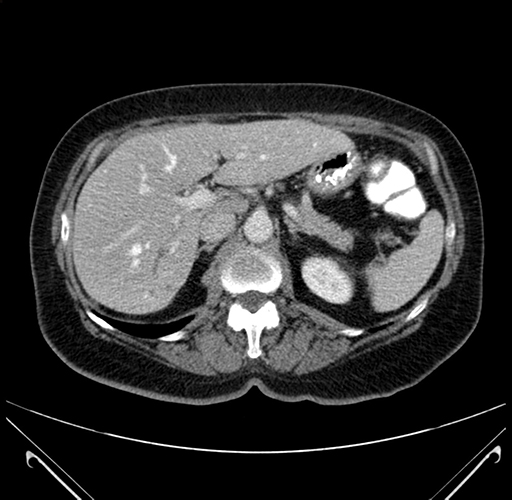

Pre-Chemo: Axial Venous

Axial Venous